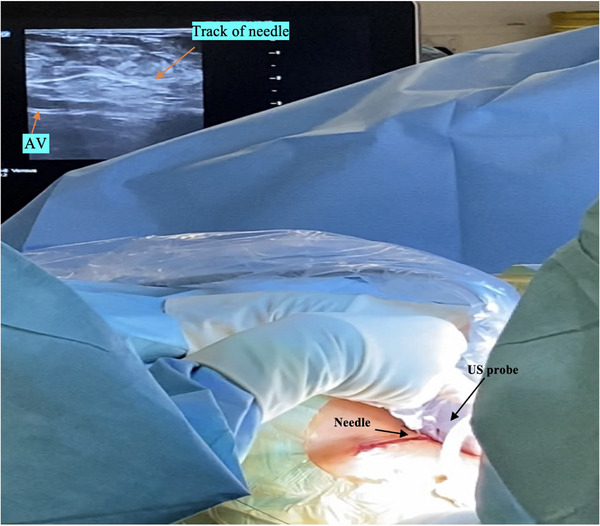

Background: There is limited real-world experience of the learning curve for ultrasound (US) guided axillary venous access for cardiac device implantation, and it is usually performed before cutaneous incision. We investigated the learning curve, radiation exposure, safety, and efficacy of US-guided venous access in standard workflow.

Methods: US-guided access was performed by an experienced electrophysiologist with no prior application of the technique by using a standard vascular US probe and minimal modification to workflow. The learning curve was evaluated using access time (needle-to-wire time). Complications were recorded until hospital discharge, and efficacy was defined by procedural success. Radiation dose savings were estimated based on fluoroscopy time for access, and a control group underwent conventional fluoroscopy landmark-guided access (n = 44 punctures).